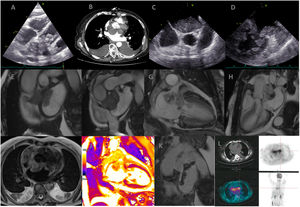

A 77-year-old woman with constitutional symptoms was admitted for acute pulmonary edema. The transthoracic echocardiography showed an intracardiac lesion (Fig. 1A) located in the left atrium (LA) and infiltrating the mitral valve leaflets, leading to severe mitral stenosis. Computed tomography and transesophageal echocardiography confirmed the transthoracic echocardiography findings (Fig. 1B–D). Cardiac magnetic resonance imaging revealed a 62mm×33mm×50mm mass in left atrium roof with irregular borders, extending to left atrial appendage and invading it (Fig. 1E–H). It extended to the atrial and ventricular surfaces of the mitral valve, with a mobile component protruding into the ventricle in diastole. The lesion showed hypersignal on T2/T1 and heterogeneous late gadolinium enhancement (LGE), ruling out a thrombus (Fig. 1I–K). Two other similar lesions were evident. She had a slight pericardial effusion with LGE of the pericardium. Chest-abdomen-pelvis computed tomography and positron emission tomography (Fig. 1L) ruled out metastasis. The tumor was unresectable and biopsy by cardiac catheterization was not possible given the risk of embolization. A lymph node biopsy was considered. However, the patient's condition rapidly worsened, with a large pericardial effusion requiring pericardiocentesis, and died in hospital. The pericardial fluid's cytology showed no neoplastic cells.

The large size, irregular borders and invasion of adjacent structures suggest a primary malignant cardiac tumor. The pericardial effusion and LGE within the tumor support the diagnosis. Sarcoma is the most likely diagnosis based on clinical and imaging findings in an immunocompetent patient (lymphoma less likely). However, a tissue sample was not obtained for anatomopathological study, and a definitive histological diagnosis was not possible.